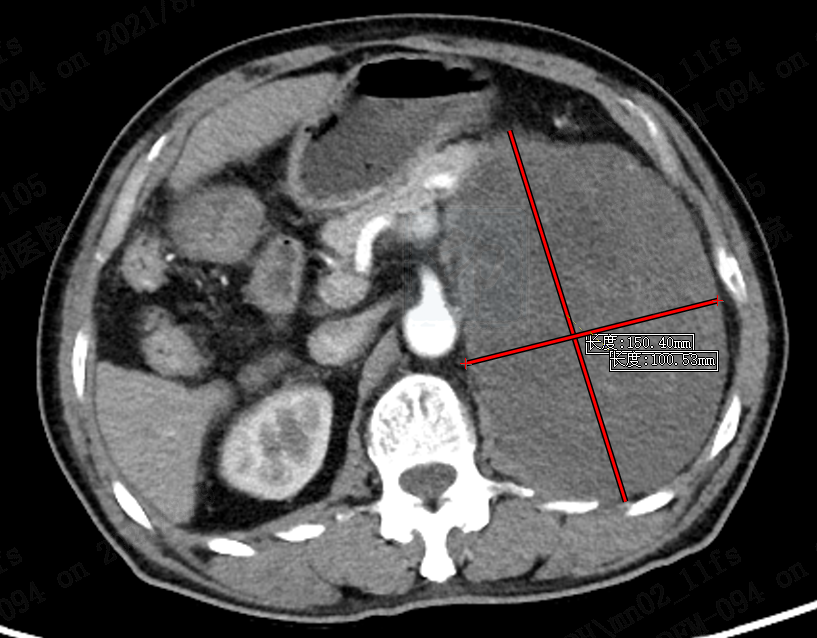

该名81岁患者近期异常消瘦,自觉左侧腹部隆起,于外院就诊,查CT提示左肾出现十余公分肿瘤。经多方咨询后到我院泌尿外科浦金贤主任门诊就诊。浦主任详细了解患者病情后,发现肿瘤位于肾脏腹侧,与胰腺及脾脏紧邻,上极达肾上腺区域,下极达骨盆入口区域,直径有15cm。